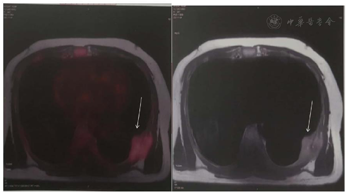

血常规:Hb 98 g/L,WBC 8.22×109/L,PLT 143×109/L,CRP 2.83 mg/L。生化:血钙2.68 mmol/L,肌酐134 μmol/L,总蛋白69.8 g/L,白蛋白52.6 g/L,球蛋白17.2 g/L,白球蛋白比:3.1,LDH 275 U/L,铁蛋白896 ng/ml,pro-BNP 983 pg/ml。胃镜:慢性非萎缩性胃炎伴胆汁反流。肠镜:直肠息肉(类圆形,直径约3 mm),已取活检,1周后拿病理报告。PET/MR(图1):左侧第7肋骨质断裂,胸壁直径4.8 cm类圆形软组织团块影,SUVmax 2.98。